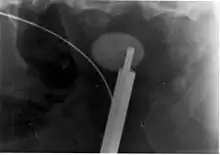

Where a CT scan is unavailable, an intravenous pyelogram may be performed to help confirm the diagnosis of urolithiasis. This involves intravenous injection of a contrast agent followed by a KUB film. Uroliths present in the kidneys, ureters, or bladder may be better defined by the use of this contrast agent. Stones can also be detected by a retrograde pyelogram, where a similar contrast agent is injected directly into the distal ostium of the ureter (where the ureter terminates as it enters the bladder).[51]